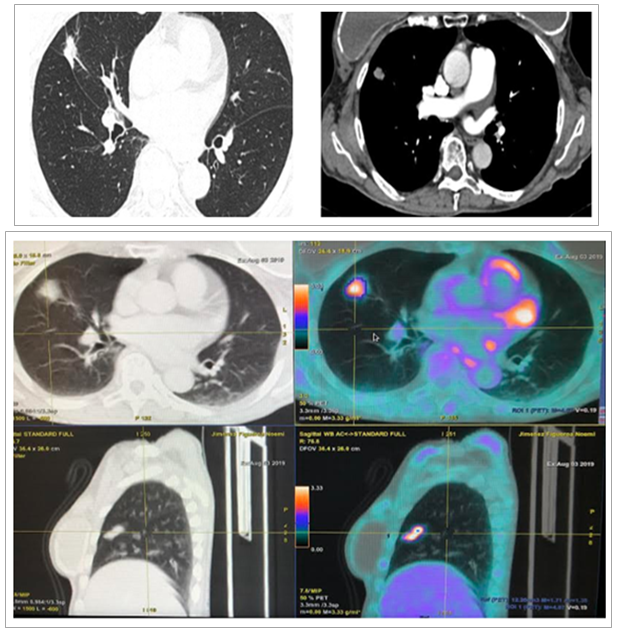

Open AccessClinical Case

Primary Lung Cancer Versus Metastasis of Thyroid Cancer the Utility of FDG PET CT

Sánchez-Ríos Carla Paola, Guzmán-Casta Jordi, Riera-Sala Rodrigo Fernando, López-Vratny Claudia, Hernández-Dehesa Itzel Ariadna, González-Araujo Andrea, Correa-Cano Rafael, Peña-Mirabal Erika, Aguirre-Pérez Natalia, Ayala-Domínguez Adriana, Elvira-Fabián Karina, Carrasco-Cara Chards Sonia, Martínez-Barrera Luis Manuel, Rodríguez-Cid Jerónimo Rafael, Alatorre-Alexander Jorge Arturo

International Journal of Innovative Research in Medical Science·December 12, 2020